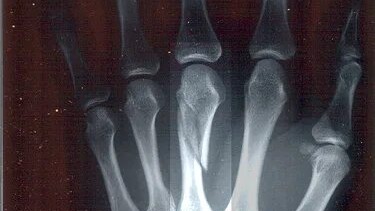

Перелом пястной кости — это травма, которая может случиться при сильном ударе, падении на руку или неправильной постановке кисти. Пястные кости играют ключевую роль в поддержании нормальной функции кисти, поэтому такие травмы требуют внимательного подхода к лечению и восстановлению. В этой статье мы расскажем, что такое перелом пястной кости, как его распознать, что делать при такой травме и как происходит реабилитация после лечения. Пястные кости — это пять костей, которые расположены между запястьем и фалангами пальцев...

Как происходят переломы пястных костей и запястья? Переломы пястных костей и запястья относятся к наиболее распространённым травмам кисти. Так как зачастую они происходят при падении на кисть — например, при занятиях спортом или при несчастных случаях во время езды на мотоцикле или велосипеде — от этих травм страдают также пациенты молодого возраста. Особенно часто при падении происходит перелом ладьевидной кости, соединяющей лучезапястный сустав с пястью. Часто при этом переломе правильный диагноз устанавливается не сразу...